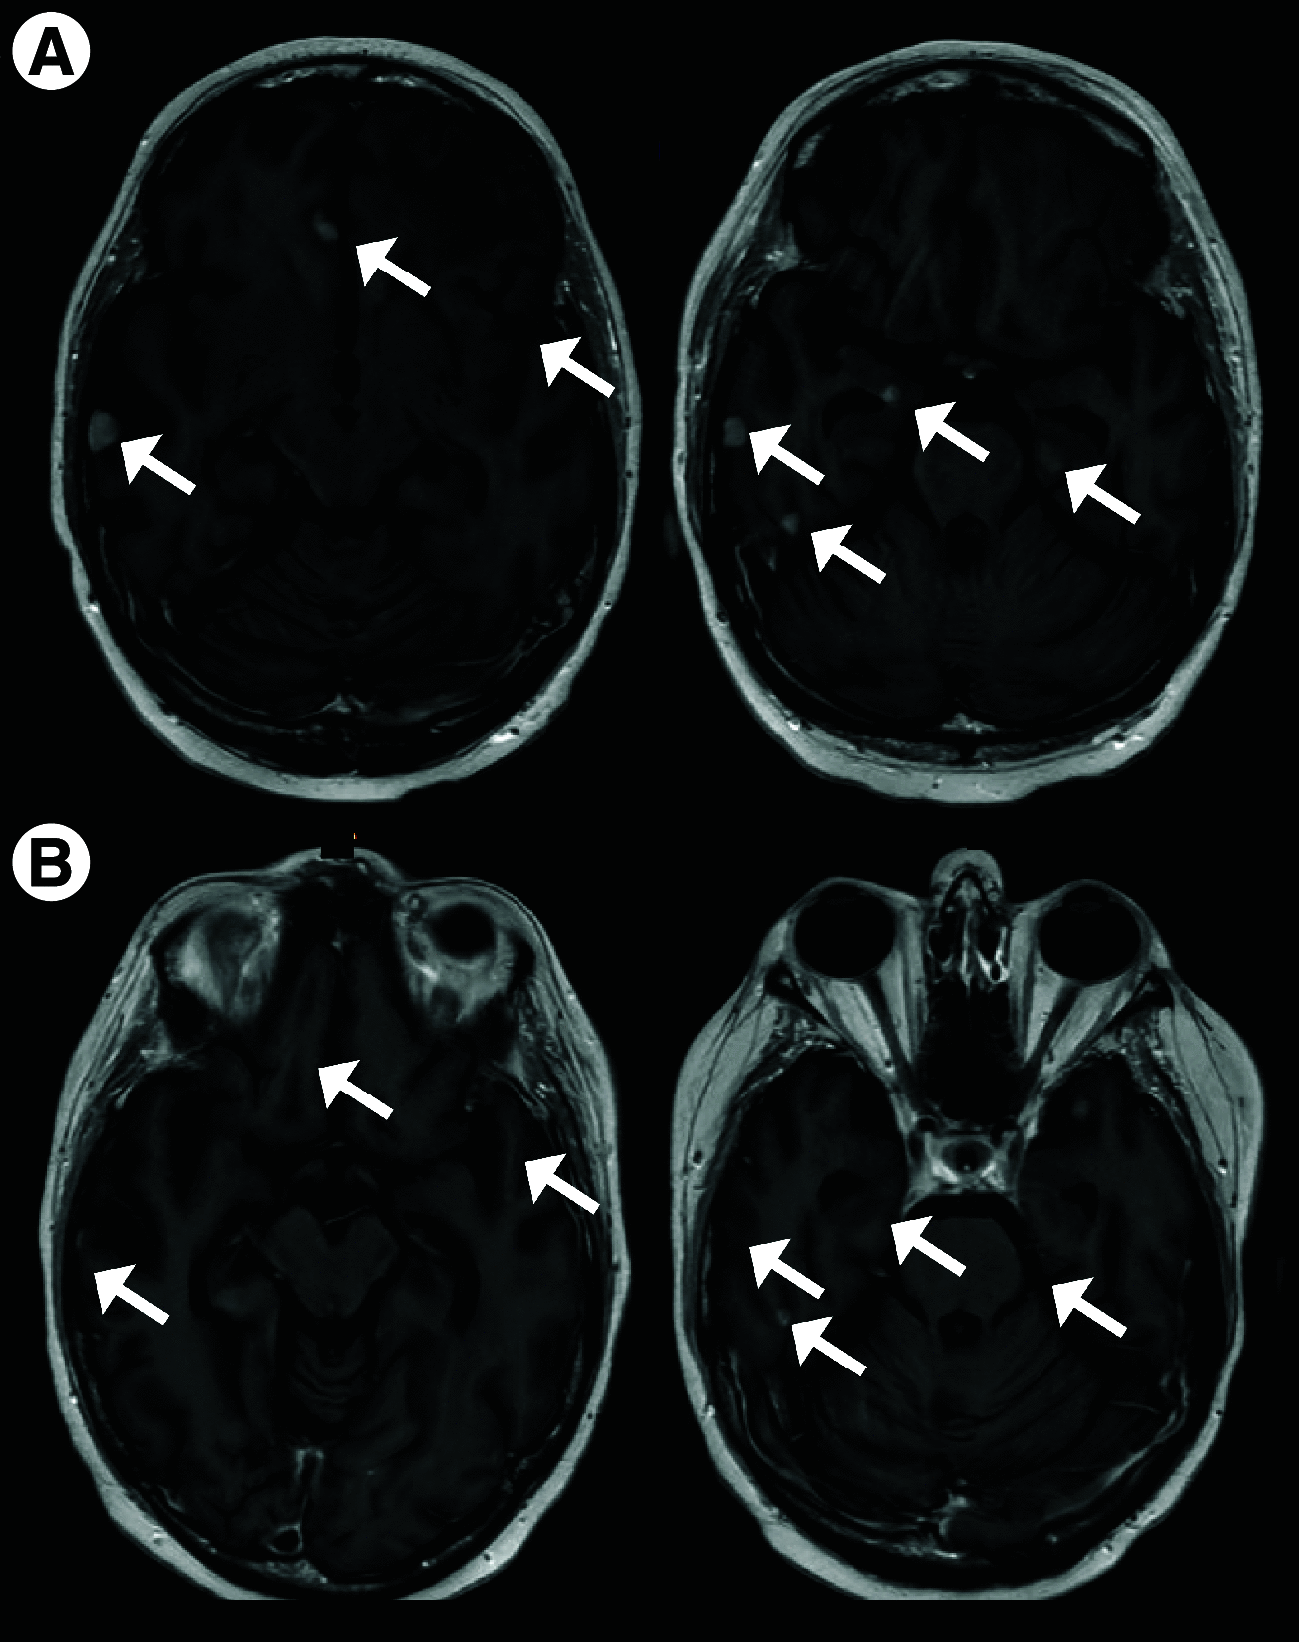

Antibody-drug conjugates have transformed the treatment of HER2+ breast and other cancers. Unfortunately, the CNS remains a sanctuary site for many such patients in part due to poor macromolecule penetration across the blood-brain tumor barrier. Trastuzumab deruxtecan (T-DXd), a high-payload antibody-drug conjugate, was recently found to improve progression-free survival in HER2+ breast cancer patients versus prior-generation trastuzumab emtansine, prompting us to evaluate CNS activity in a woman with brain-only metastatic disease. T-DXd achieved complete response despite heavy pretreatment. Three persistent, previously-irradiated lesions were biopsy-proven to represent treatment effect. Subsequent recurrence occurred upon treatment holiday; partial response was observed with rechallenge. This case suggests T-DXd is active in HER2+ breast cancer brain metastases and supports further prospective evaluation.